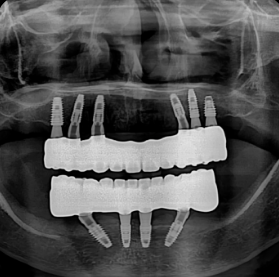

ALL IMPLANT VS FULLARCH

전체임플란트 vs 풀아치

나에게 꼭 맞는 치료법은?

“저도 풀아치를 할 수 있을까요?” 무조건 풀아치를 권하지 않습니다.

환자분께 가장 좋은 치료가 저희에게도 가장 좋은 치료이기 때문입니다.

풀아치가 필요한 경우

틀니를 오래 사용하셨거나, 잇몸뼈가 전반적으로

많이 내려앉아 치아만 만들 경우

너무 깊이 보이는 분들에게 가장 이상적입니다.

전체 임플란트가 더 나은 경우

치아를 뺄 지 않아도 잇몸뼈가 충분히 남아있는 분들은

잇몸 뼈를 삭제할 필요 없이, 치아만 만드는

전체 임플란트가 더 적합할 수 있습니다.